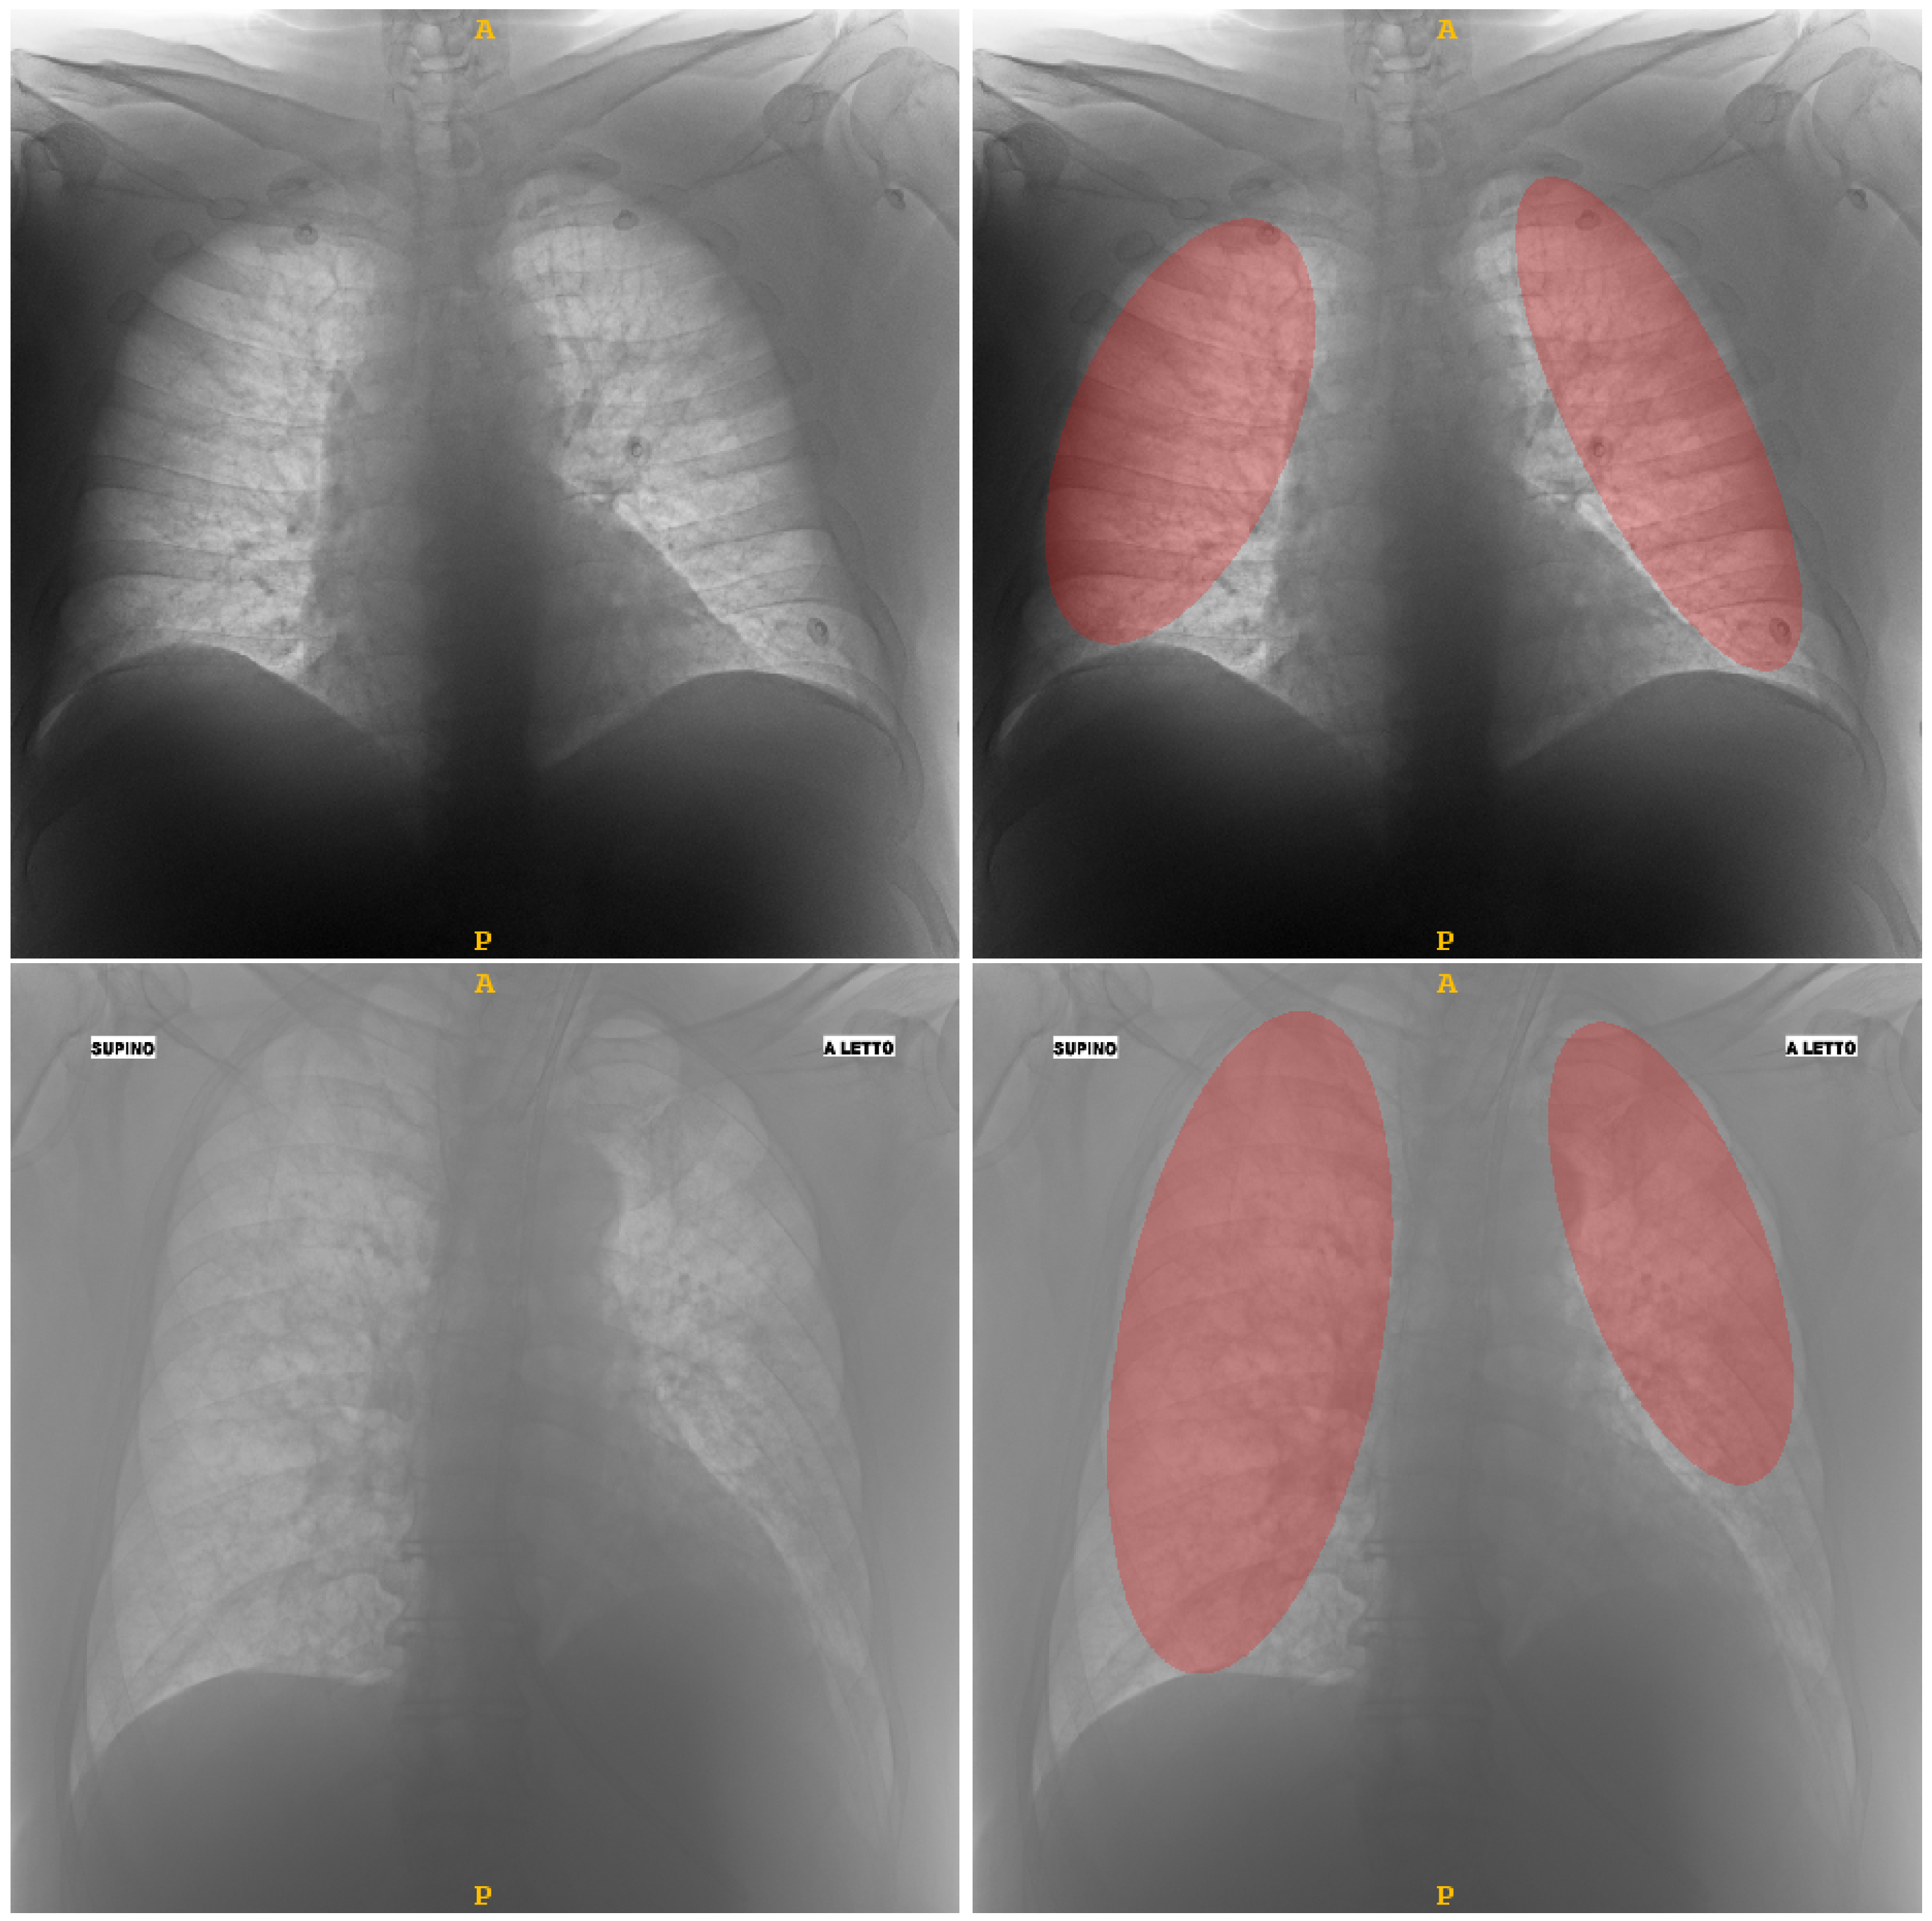

2.1. Dataset Characteristics and Lung Delineation